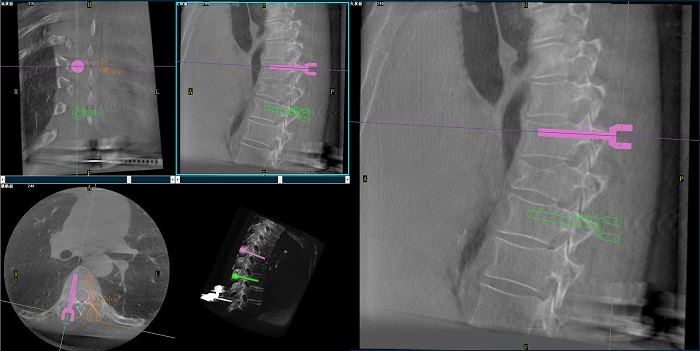

②机器人辅助胸椎手术操作难点之路径规划

人体胸椎的椎弓根较腰椎更狭窄,周围有重要的神经和血管,选择合适尺寸和长度的螺钉至关重要。螺钉过粗可能损伤椎弓根,过细容易发生形变,固定强度不够;螺钉过长可能穿透椎体前缘,造成损伤,过短则固定不牢。

普爱医疗手术导航定位系统解决方案

使用机器人辅助手术,医生不仅可以在影像的引导下,一次性完成多枚螺钉的路径规划,提高手术效率,而且可以精确地选择螺钉的角度、直径和长度,提高手术的成功率。